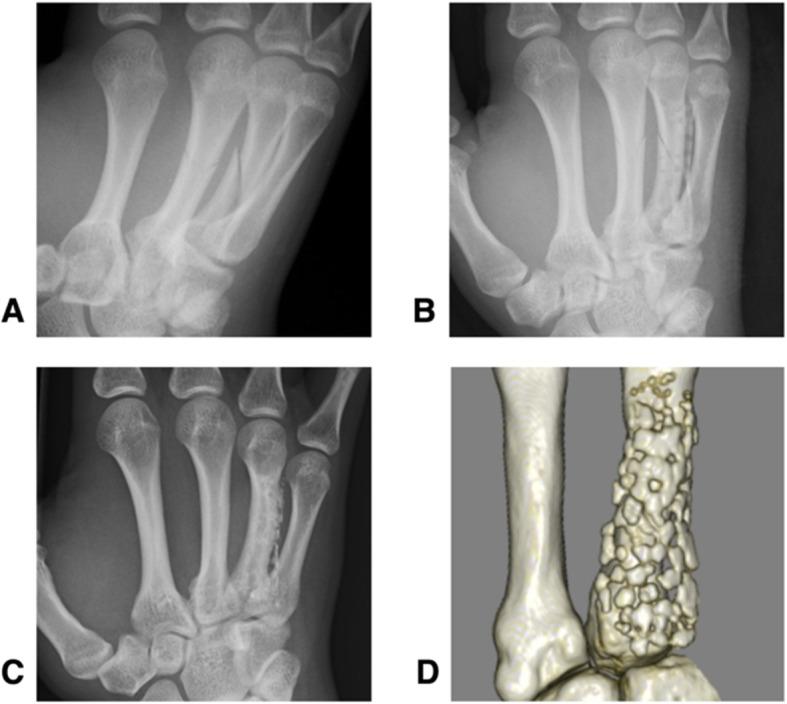

Implants made from bioabsorbable unsintered hydroxyapatite and poly-L-lactate composites (u-HA/PLLA) are widely used in the oral, maxillofacial, and orthopedic fields. This study assess the long-term (> 5 years) outcomes of patients with metacarpal fractures who were surgically treated using bioabsorbable plates and screws (Super-Fixsorb MX40 mesh; Teijin Medical Technology, Osaka, Japan).

A retrospective analysis of six patients with eight metacarpal fractures treated with bioabsorbable plates was done. All patients were followed for more than 5 years post-surgery. The clinical outcomes were evaluated using Q-DASH scores and the grip strength (GS): opposite side ratio. The resorption status of implants was assessed on plain computed tomography (CT) scans at final follow-up appointments.

The mean age of the patients at the time of surgery was 29.5 years (16-54), and the median follow-up period was 81.8 months (68-101). All fractures united without displacement after an average of 3.5 months, and there were no implant specific complications associated with the use of absorbable plates. The mean grip strength ratio was 85.1% (56.8-104.5). The mean Q-DASH scores of 11.36 points (0-34.09) was good in all but two patients. We also observed that it took more than 8 years for the plates to be absorbed completely.

由可吸收的未烧结羟基磷灰石和聚 L-乳酸复合材料(u-HA/PLLA)制成的植入物广泛应用于口腔、颌面和骨科领域。本研究评估了使用可吸收板和螺钉(Super-Fixsorb MX40 网;日本帝人医疗技术公司)治疗掌骨骨折患者的长期(>5 年)结果。

对 6 例 8 处掌骨骨折患者使用可吸收板进行回顾性分析。所有患者术后随访时间均>5 年。使用 Q-DASH 评分和握力(GS):对侧比值评估临床结果。在最后一次随访时,通过平扫 CT 评估植入物的吸收情况。

手术时患者的平均年龄为 29.5 岁(16-54 岁),中位随访时间为 81.8 个月(68-101 个月)。所有骨折在平均 3.5 个月后均无移位愈合,且无与使用可吸收板相关的特定植入物并发症。平均握力比为 85.1%(56.8-104.5)。11.36 分(0-34.09)的平均 Q-DASH 评分在除两名患者外的所有患者中均良好。我们还观察到,板的完全吸收需要超过 8 年的时间。